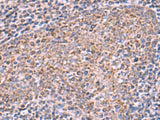

ECSIT Polyclonal Antibody Reactivity Human

Reactivity Human

Applications IHC

IHC 1:50-1:300